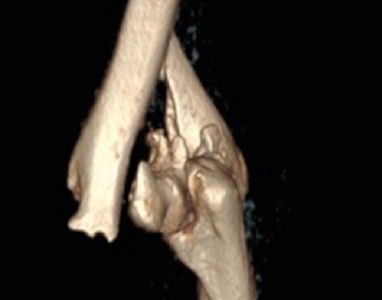

Figure 3.Right elbow CT scan with 3D reconstruction at admittance in the emergency department.

A 70-year-old woman was admitted in San Jacopo Hospital in the Pistoia emergency department with the injury of the right elbow due to blunt trauma reported after a fall while she was walking home. X-ray (Fig. 2) and CT (Fig. 3) showed a supracondylar right humerus multiple fragment fracture with articular elbow dislocation. We classified the fracture as 13C3.1 according to the AO classification.